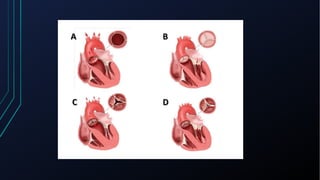

Dor torácica pode ter diversas causas, incluindo cardíacas como síndrome coronariana aguda, dissecção de aorta e pericardite, e não cardíacas como problemas pulmonares, musculoesqueléticos e do trato gastrointestinal. É importante avaliar a história clínica, características da dor e exame físico para identificar a possível causa e orientar o tratamento adequado.